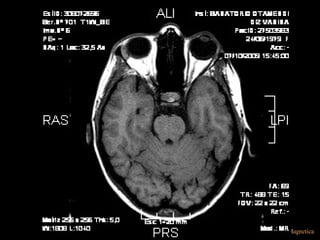

*STIR (SHORT TIME INVERSION RECOVERY)

• TI= CORTO PARA SATURAR LA GRASA,

• Útil para evaluar y diferenciar un componente

liquido de grasa

IR

ALEJANDRA GALVEZ